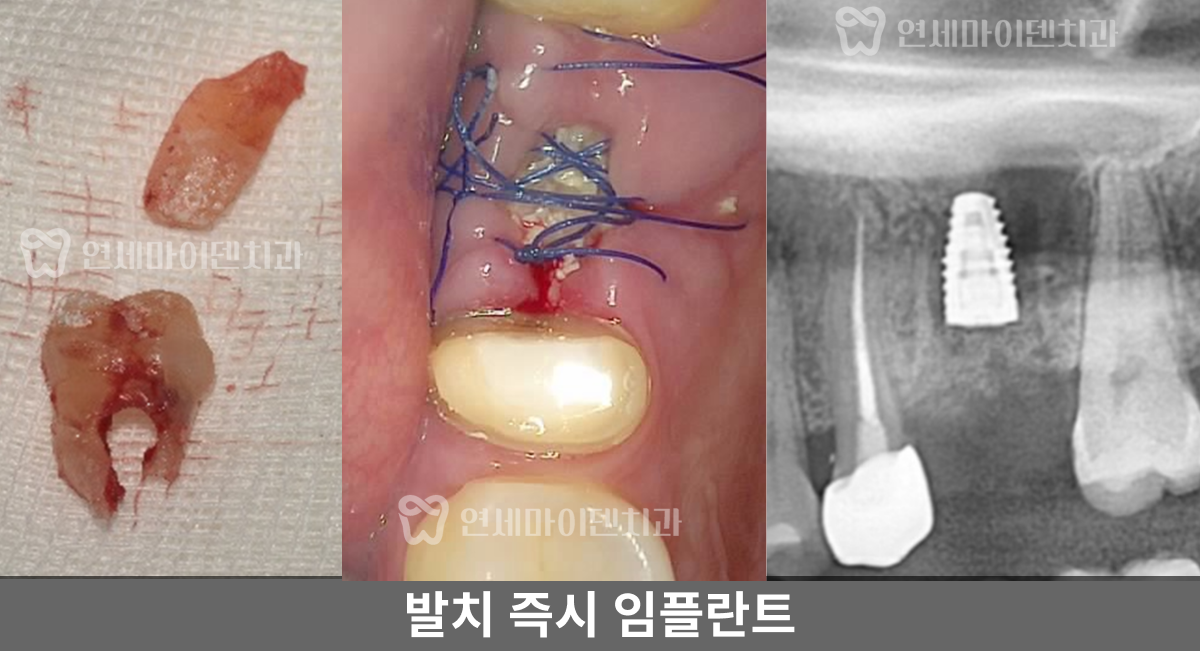

앞쪽 작은 치아는 재신경치료를 잘 마무리 했으나, 뒤쪽 치아는 기존 보철을 제거하자 안쪽에서 계속해서 피가 나오는 상황이었습니다.

■ #26번, 두 번째 치아 치료 -발치 즉시 임플란트

먼저 CT를 촬영하고 시작했어야 했는데, 나중에 CT를 확인해보니 구개측 뿌리에 퍼포레이션(뚫림)이 발생해 있었습니다.

이 치아는 세개의 뿌리가 있는데, 구개측 뿌리의 신경관 중간부에 구멍이 뚫려있었고 그 부위의 뼈에서 염증으로 인한 출혈이 계속 올라오고 있었습니다.

뼈가 상당히 손실된 상태였습니다. 만약 뼈 소실이 심하기 전에 이 구멍을 MTA라는 특수 재료로 처치했다면, 치아를 살릴 수 있었을 텐데 그 시기를 놓쳐 뿌리 절제술을 하거나 발치 후 임플란트 중 하나를 선택해야 했습니다.

환자분께 현재 상태와 두 가지 옵션을 설명드렸고, 환자분께서 임플란트를 선택하셔서 '발치 즉시 임플란트'를 진행했습니다.

■ #26번, 발치 즉시 임플란트 수술 과정